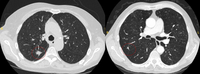

Tomografia computadorizada (TC) mostrando um pequeno nódulo no lobo superior esquerdo com margens lisas, posteriormente considerado uma metástase colorretal solitária na ressecção

Cortes de tomografia computadorizada (TC) com exemplos de nódulos solitários semissólidos